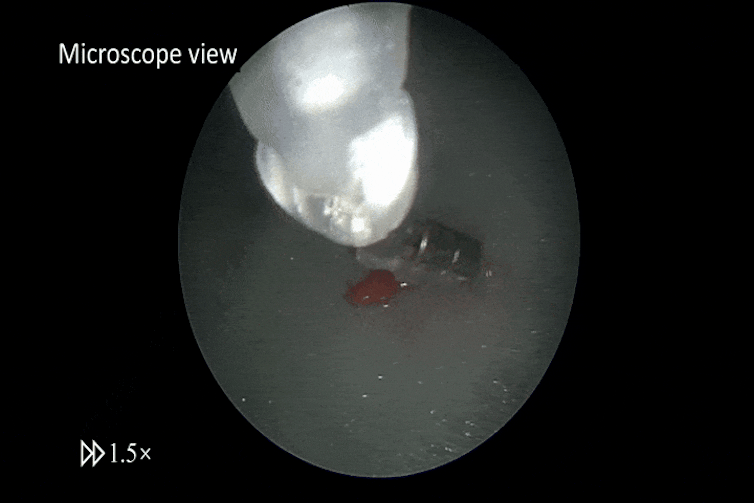

The tools are only about 3mm in diameter. In a paper published in Science Robotics, we demonstrated these tools could grip, pull and cut tissue.

We tested the tools in pre-clinical trials where we simulated the mechanical properties of the brain tissue they would need to work with. In some tests, we used pieces of tofu and raspberry placed inside a model of the brain.

We compared the performance of these magnetically operated tools with that of standard tools handled by trained surgeons.

We found the cuts made with the magnetic scalpel were consistent and narrow, with an average width of 0.3–0.4mm. That was even more precise than those from traditional hand tools, which ranged from 0.6 to 2.1mm.